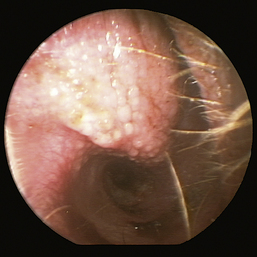

Figure 20-16, p. 596, Ceruminal gland adenoma in the external ear canal of a dog

image

Figure 20-16 Ceruminal gland adenoma with blood noted in the external ear canal of a dog.

(Courtesy of Dr. Lynette Cole, The Ohio State University, Columbus, Ohio.)